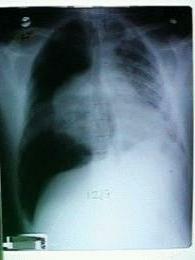

Click CXR to see enlarged version. Would you like to see the AXR, or proceed?

4. Insert a chest tube into the left pleural cavity

5cxr